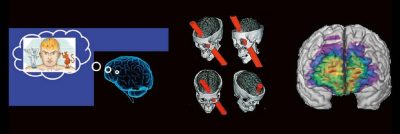

Categories: WebinarOutside the box-Vortrag: die Neuroradiologie der Moral (Webinar | Online)

Professor Dr. med. Michael Knauth Das Treffen moralischer Entscheidungen erfordert – wie jede andere Hirnleistung auch – das Zusammenwirken verschiedener Hirnareale. Der Vortrag nimmt auf eine interaktive Reise durch die Mehrzügeligkeit moralischer Entscheidungen (emotional vs. utilitaristisch) und gängiger moralischer Dilemmata (Trolley-Problem) und führt schließlich zu den mit dem Treffen dieser Entscheidungen befassten Hirnregionen und zu den Auswirkungen auf moralische Entscheidungen […]